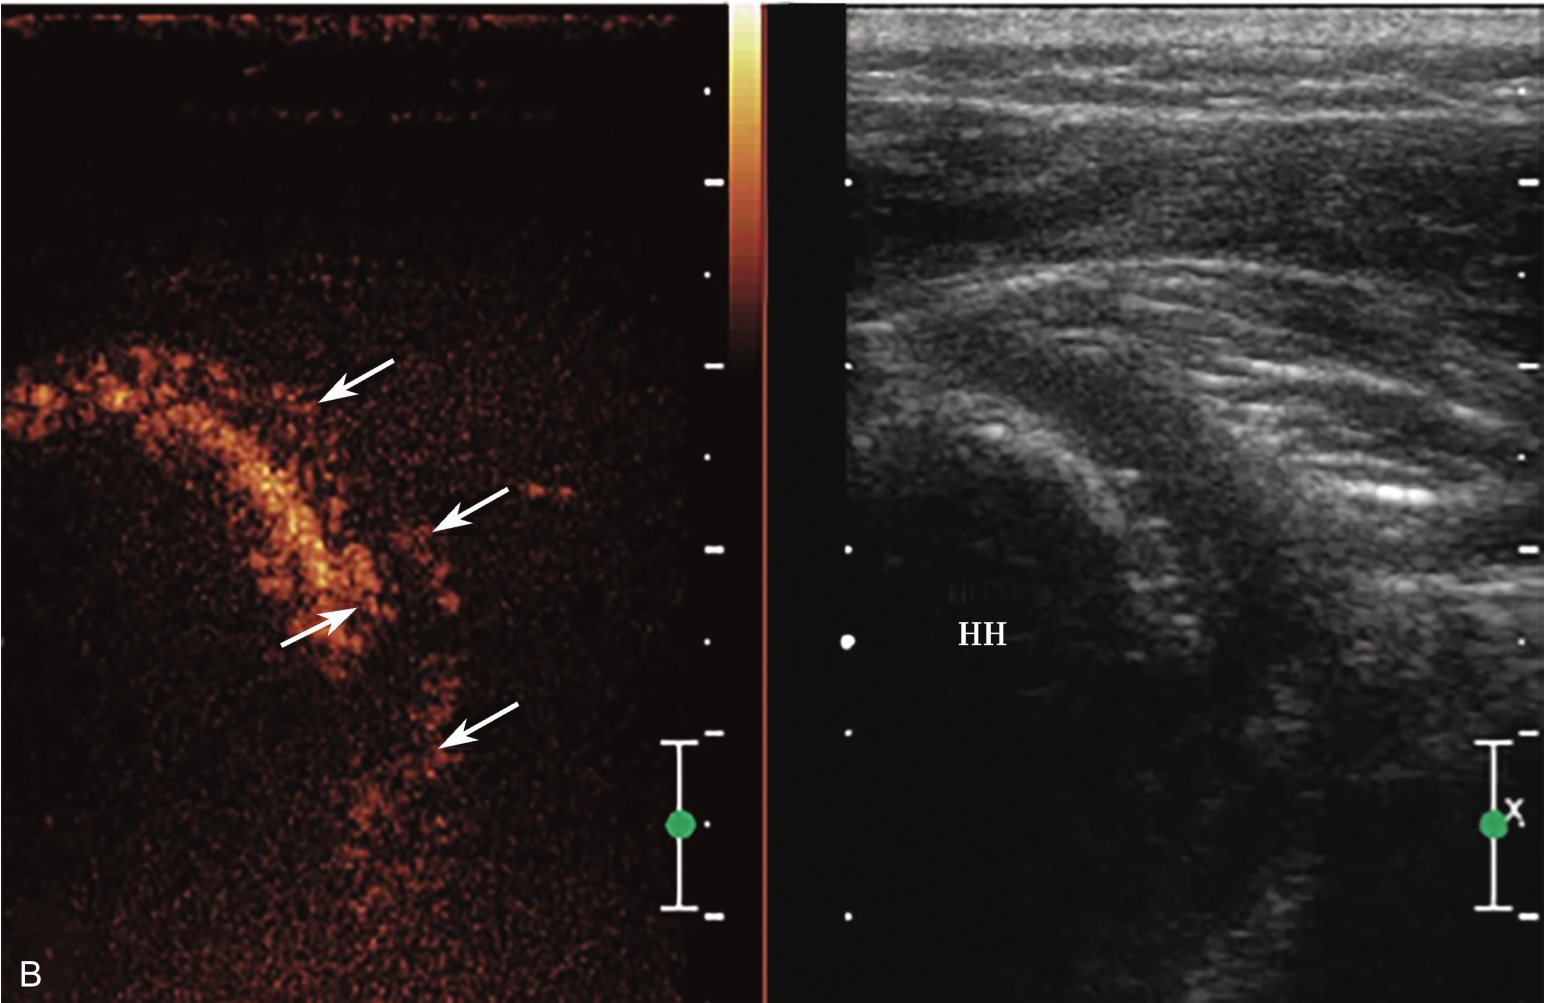

▲ 图2-6-6 超声引导下肩关节腔介入治疗超声图(四)

A.超声引导下穿刺针进入盂肱关节;B.注射治疗后扩张的关节腔;C.注射治疗后关节腔内粘连带;单星号:关节腔;三星号:关节腔内粘连带;箭头:穿刺针